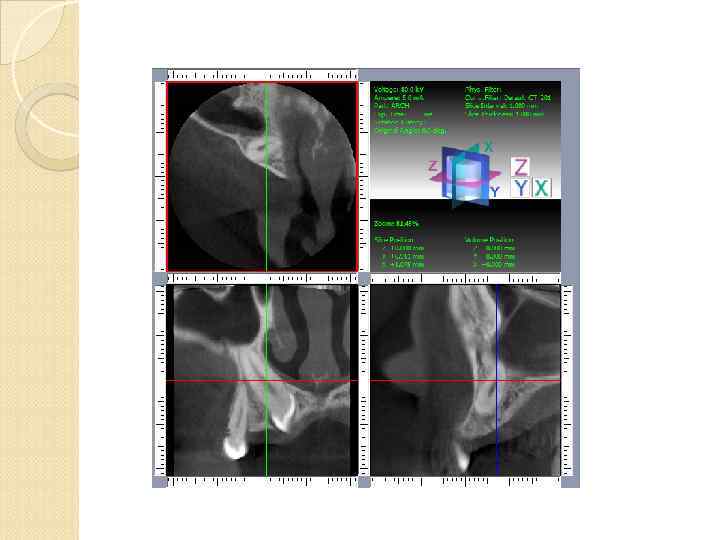

Специализированные стоматологические томографы для сканирования вместо тысяч точечных детекторов используется один плоскостной сенсор. генерируемый луч коллимируется в виде конуса. рассчитаны на детальное исследование костной ткани и твердых тканей зубов Мягкие ткани

Специализированные стоматологические томографы для сканирования вместо тысяч точечных детекторов используется один плоскостной сенсор. генерируемый луч коллимируется в виде конуса. рассчитаны на детальное исследование костной ткани и твердых тканей зубов Мягкие ткани

ACCUITOMO фирмы Morita (Япония) программное обеспечение, слабо адаптированное к стоматологии, практически стандартный общемедицинский DICOM-просмотрщик.

ACCUITOMO фирмы Morita (Япония) программное обеспечение, слабо адаптированное к стоматологии, практически стандартный общемедицинский DICOM-просмотрщик.

Томограф PICASSO-Trio производить все виды рентгенографии, используемой в стоматологии: компьютерная томография, телерентгенография, панорамная томография зубных рядов (ортпантомография).

Томограф PICASSO-Trio производить все виды рентгенографии, используемой в стоматологии: компьютерная томография, телерентгенография, панорамная томография зубных рядов (ортпантомография).

GALILEOS оснащен специализированными стоматологическими программами

GALILEOS оснащен специализированными стоматологическими программами

Инородное тело гайморовой пазухи пломбировочный материал

Инородное тело гайморовой пазухи пломбировочный материал

Инородное тело гайморовой пазухи пломбировочн

Инородное тело гайморовой пазухи пломбировочн